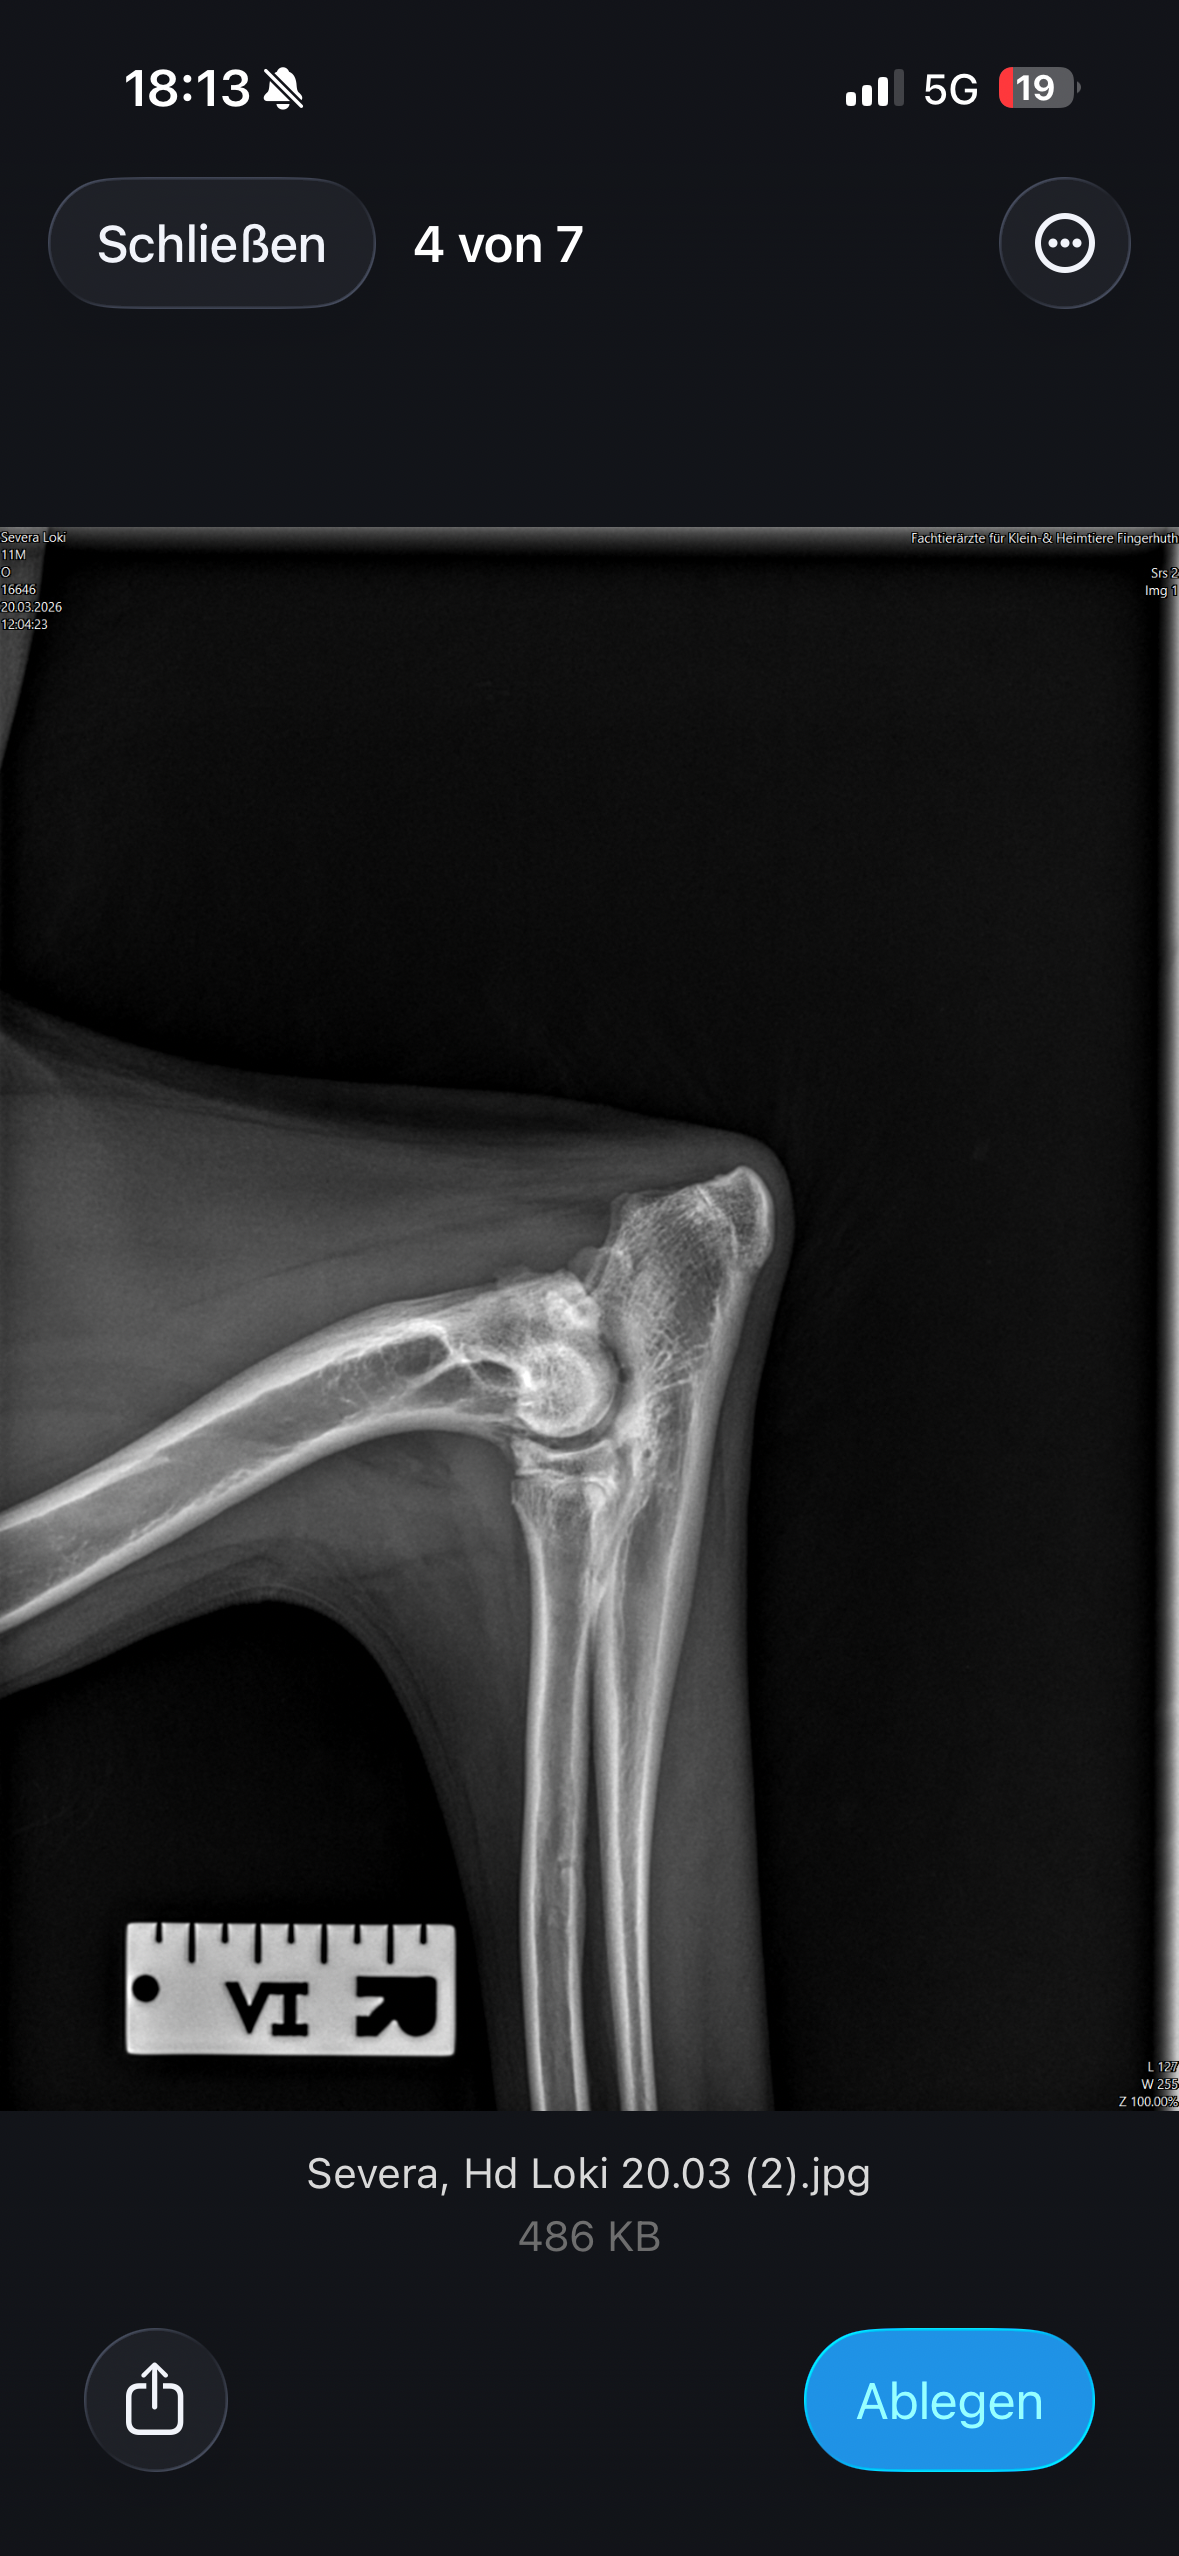

Loki leidet an Ellenbogendysplasie und Hüftdysplasie, jeweils auf beiden Seiten, was mehrere große und schwere Operationen erfordert, um ihm ein „so gut es geht“ schmerzfreies Leben zu ermöglichen. Die Gesamtkosten für die erforderlichen Behandlungen belaufen sich auf etwa 20.000 €, zu denen zusätzlich Behandlungskosten von mindestens 10.000 € für Physiotherapie, Medikamentengabe und weitere Maßnahmen kommen.

Röntgen, CT, Blutuntersuchung,mind. 3 große OP’s, Künstliche Hüftgelenke beidseits, Schmerzmittel, Physio, Wasserlaufband